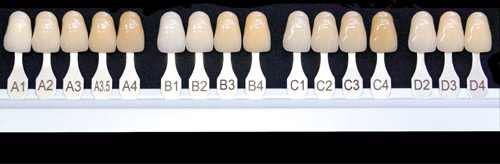

セルフホワイトニングやオフィスホワイトニングの施術をする際はシェードガイド(色見本)を用いて今の自分の歯の色や希望の白さを確認します。また、エステやサロンでのセルフホワイトニングではご自身の歯の本来の白さまで戻せるのに対し、歯科医院でのオフィスホワイトニングはご自身の歯の色より白くすることも期待できます。歯科医院では医療機関でしか取り扱えない薬剤や医療機器を使っているからです。

日本人の歯の白さ

日本人のもともとの歯の色は少し黄味がかかった白い色をしており、シェードガイドではA3.5になります。一般的にA1より白くなるとより白くなったと感じやすくなります。また、モデルや芸能人の歯の白さはA1以上の方が多くいらっしゃいます。

カウンセリングではシェードガイドを使いながら歯のお悩みをお伺いします。ご予算などもうかがった上で歯科医師と歯科衛生士がご希望に即した治療プランをご提案いたします。カウンセリングは無料です。